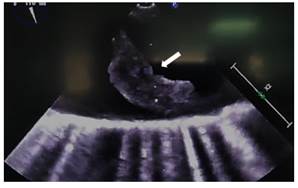

En búsqueda de fuente embólica se realiza un ecocardiograma transesofágico (ETE) (ver Figura 3 y 4 ), donde se evidenció placas ulceradas penetrantes en cayado aórtico distal y aorta descendente proximal de 9 mm con trombo móvil de 22 mm y 4 mm de espesor. A 4,5 cm de esta lesión en aorta descendente proximal, se aprecia una úlcera penetrante de 15 mm con gran trombo móvil de 35x9x11 mm.

Figura 3 Ecocardiograma transesofágico: la flecha indica la placa ulcerada con trombo móvil de 22 mm X 4 mm de espesor en aorta.